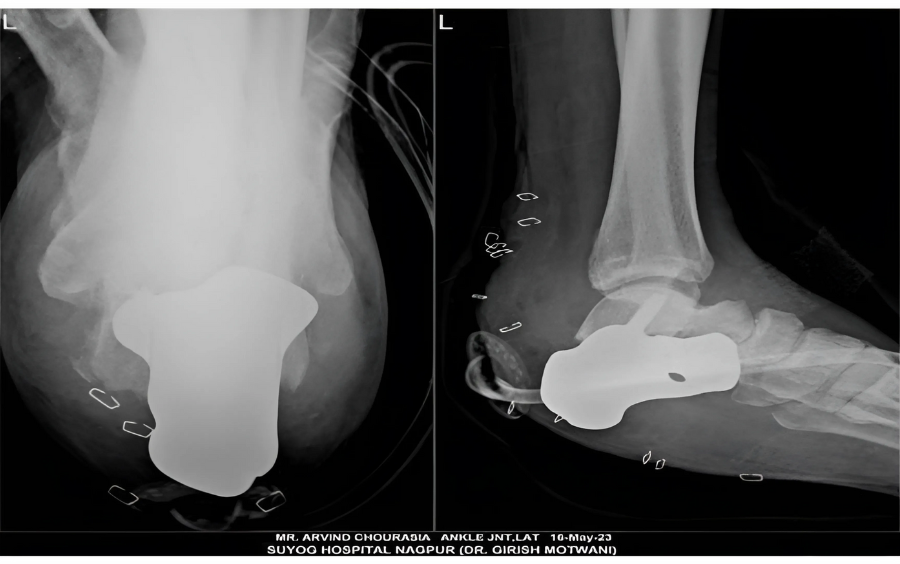

The implant was manufactured under ISO 13485 guidelines & tested to give an accurate fit & utmost safety. Once the resection was done, a customized implant from 3D Incredible was implanted.

Utilizing advanced technologies, such as 3D printing, has made it possible to create an implant that is specifically customized to fit the patient's anatomy. This example highlights how important customized surgical strategies, advanced methods, and the proficiency of skilled surgeons are to get the best outcomes possible for complicated foot diseases. Read more